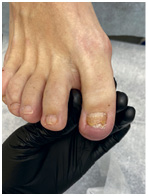

Хирург не заботится об эстетической стороне вопроса. Ему важно решить проблему, чтобы вы больше не испытывали дискомфорт. Часто после хирургического лечения ноготь меняет форму, становится менее красивым – к этому нужно быть готовым.

Иллюстрация к книге — Подология понятно. Важен каждый шаг. Справочник по проблемам подологии для клиентов и мастеров эстетики [i_269.jpg]

Иллюстрация к книге — Подология понятно. Важен каждый шаг. Справочник по проблемам подологии для клиентов и мастеров эстетики [i_270.jpg]

Иллюстрация к книге — Подология понятно. Важен каждый шаг. Справочник по проблемам подологии для клиентов и мастеров эстетики [i_271.jpg]

Иллюстрация к книге — Подология понятно. Важен каждый шаг. Справочник по проблемам подологии для клиентов и мастеров эстетики [i_272.jpg]

Результат работы за 5 месяцев: подолог использовал крючковые коррекционные системы, а хирург сделал пластику внутреннего бокового валика (из-за хронических воспалений боковой валик стал гипертрофированным и давил на ноготь, от чего клиент испытывал постоянный дискомфорт)